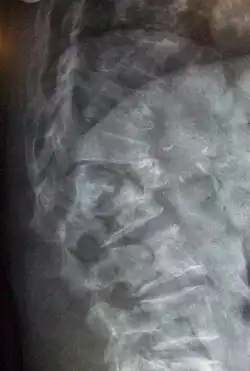

| Lateral spine X-ray showing osteoporotic wedge fractures of L1/2 | |